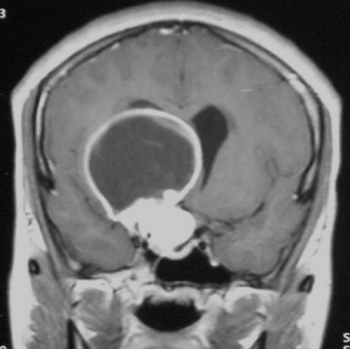

Astrositom